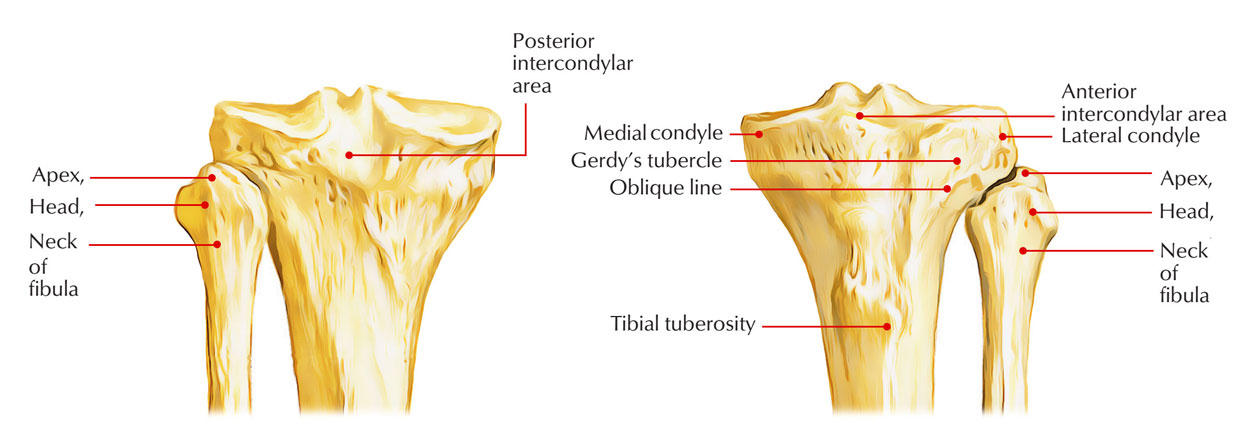

Анатомия фибулы: Подробные фотографии и схемы